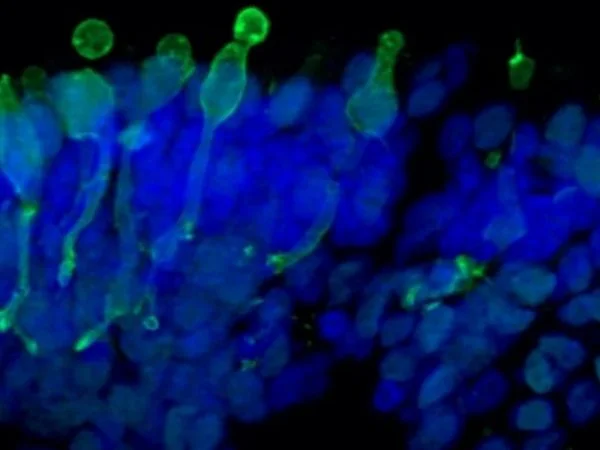

Cone photoreceptor cells labeled with anti-Opsin (Red/Green) antibody. Image Credit: Newcells Biotech

Cone photoreceptor cells labeled with anti-Opsin (Red/Green) antibody. Image Credit: Newcells Biotech

With a laminar cell organization resembling embryonic development, the retinal organoids, derived from iPSCs, replicate the intricate structure of the human retina. They contain the retina’s light-responsive outer photoreceptor segment.